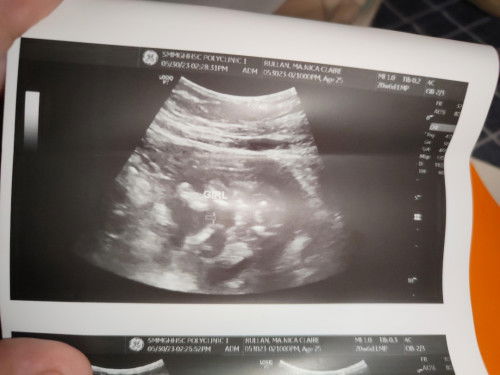

Gender Ultrasound

Accurate na po ba ito na baby Girl ? 20 weeks and 6 days po ako nagpa ultrasound po . Pa check naman po sa mga marunong po hehehe..

Yes mamsh, if hnd kapa satisfied sa gender reveal ni baby pwede ka nmn mag pa CAS dun malinaw tlaga ung gender reveal ni baby and para ma check mona din si baby sa loob at lahat ng organs nya kung normal..

mukhang burger bun po. girl nga po. ☺